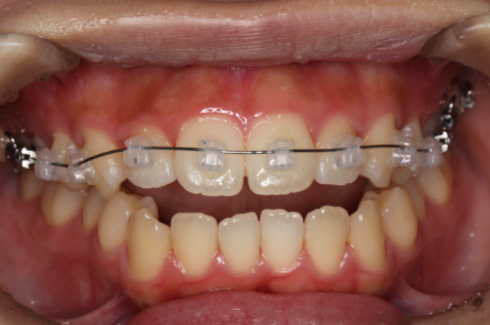

歯を動かすためにワイヤーの力を利用して歯の移動を行う装置を、マルチブラケットアプライアンスと呼びます。

セルフライゲーションブラケット装置(デーモンクリア)、歯の裏側に装着するカスタムメイド型リンガルブラケット等の種類があります。

2期治療では、永久歯列完成頃に歯並び咬み合わせ全体の治療を行います。

12~14歳頃(顎の成長に問題が無い時点)から、本格的な歯列全体の治療を行っていきます。